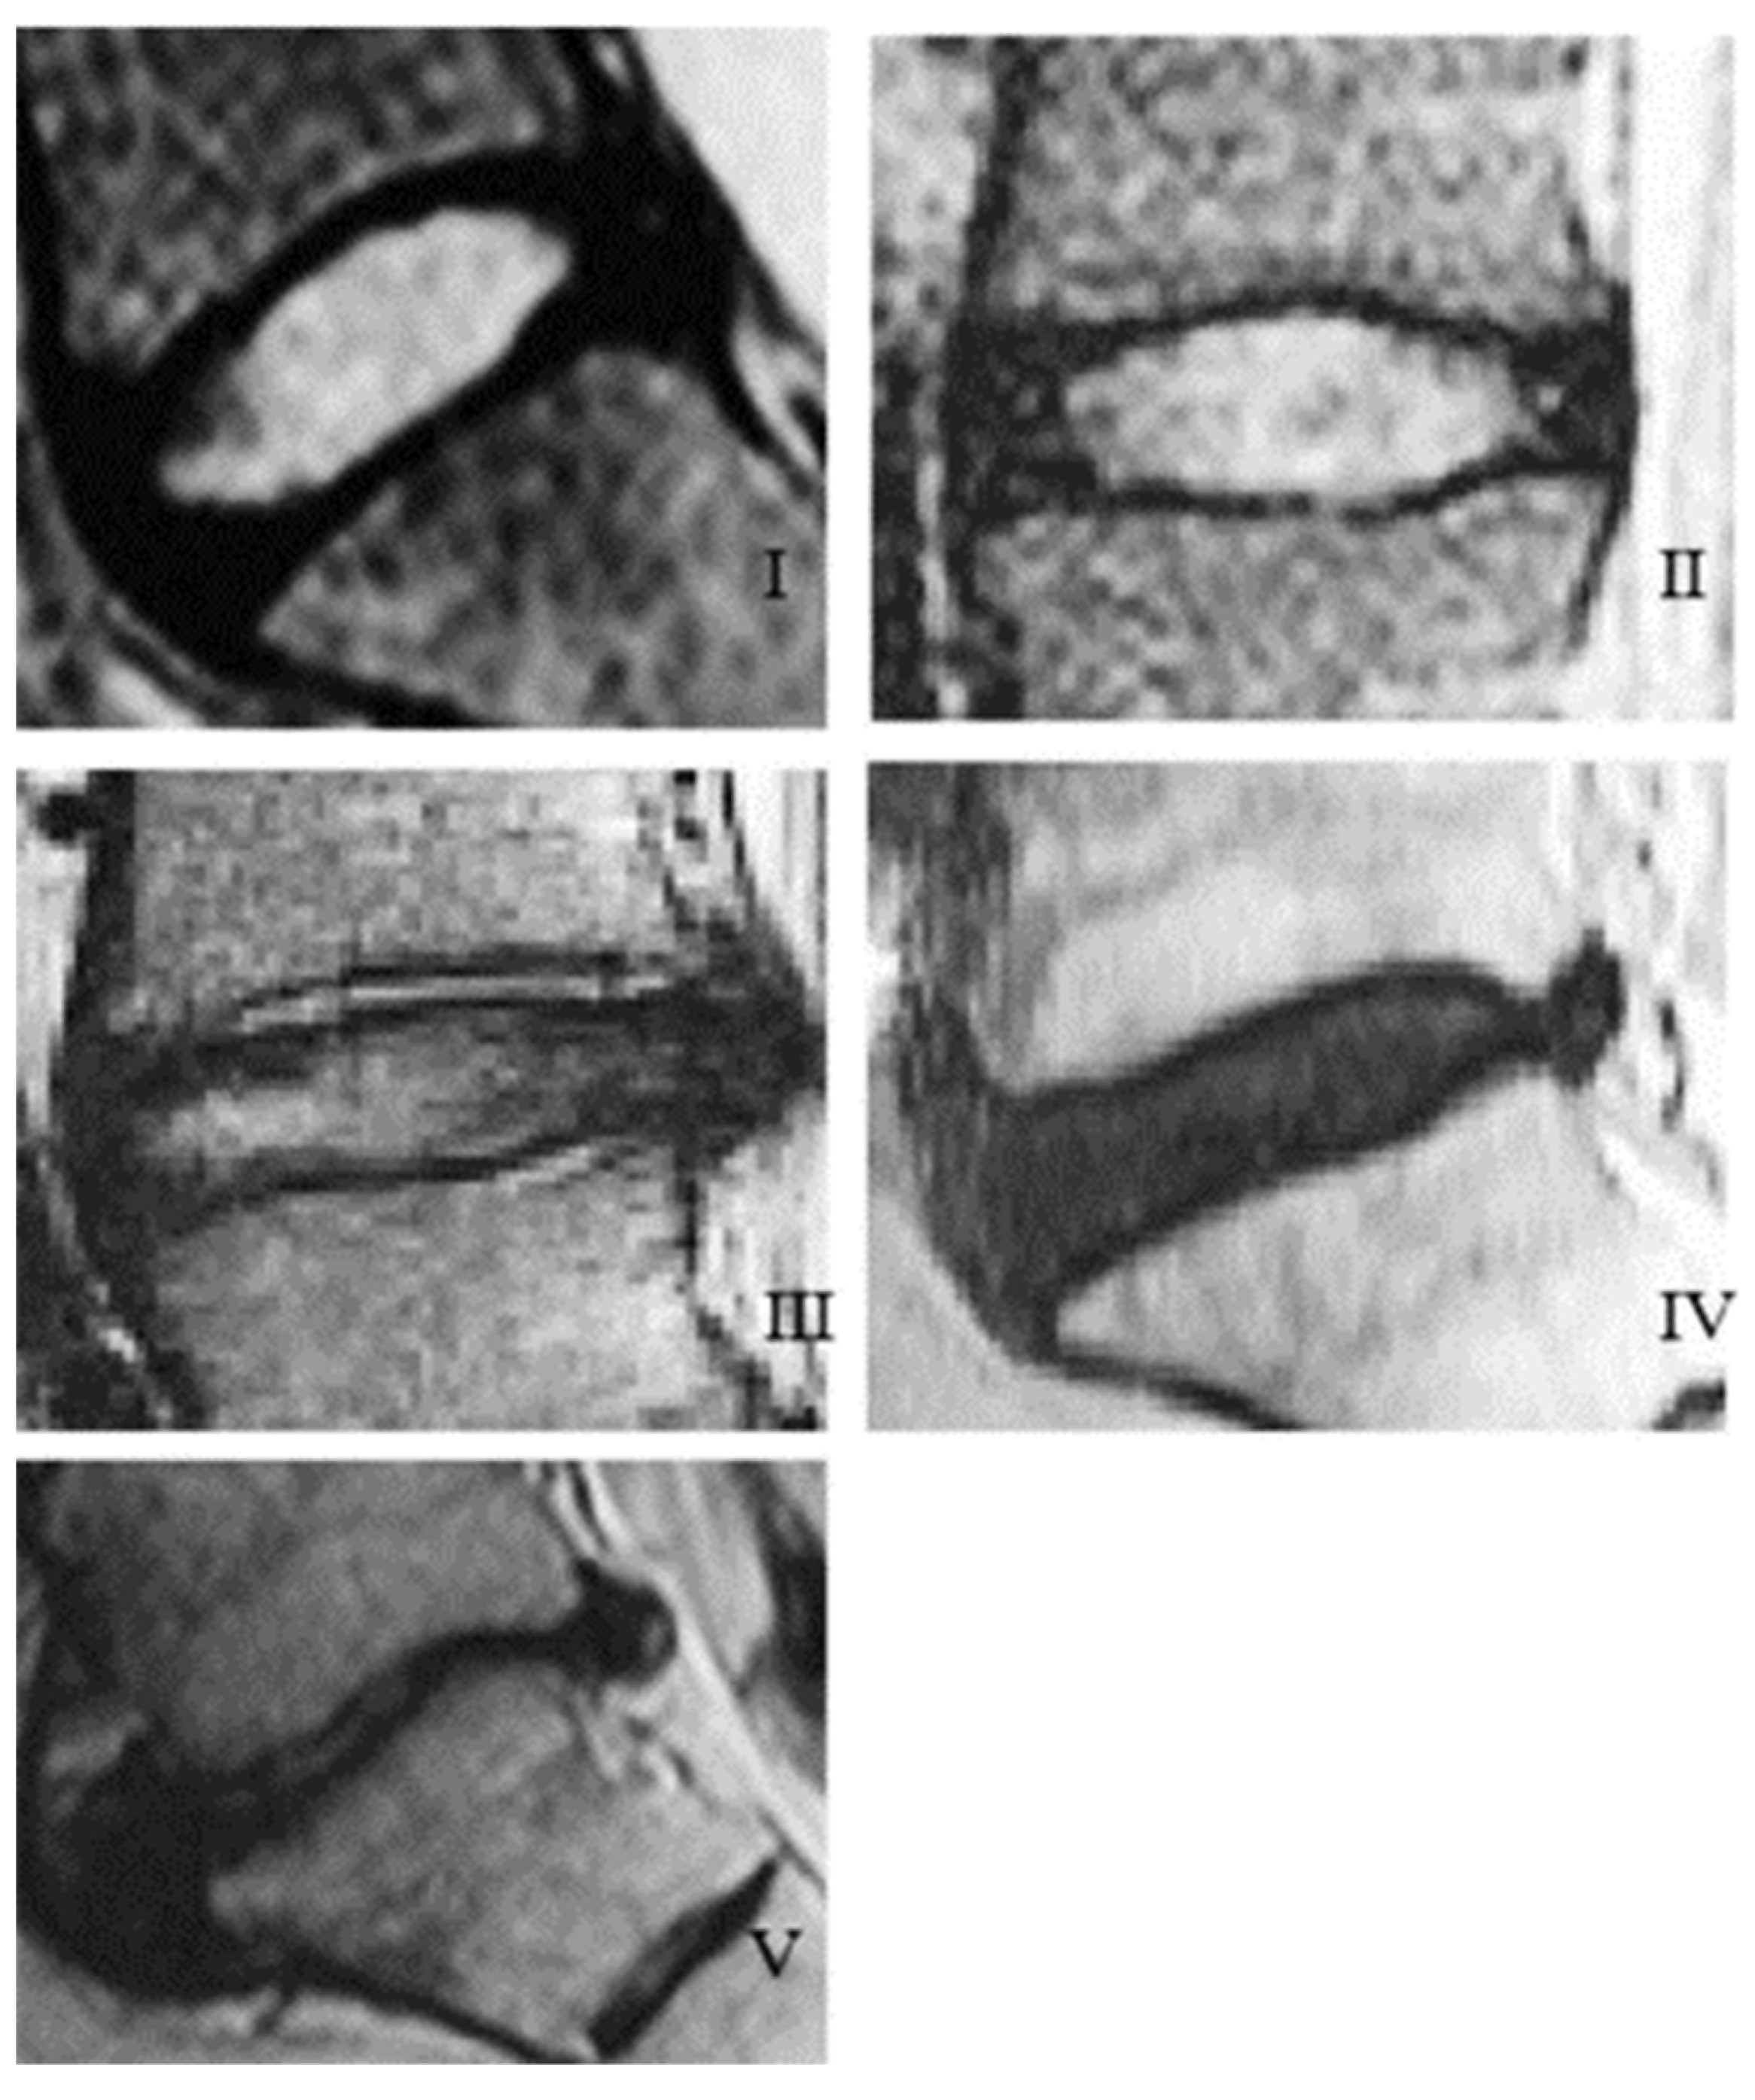

| Grade | Structure | Distinction of Nucleus and Annulus | Signal Intensity | Height of Intervertebral Disc |

|---|---|---|---|---|

| I | Homogenous, bright white | Clear | Hyperintense, isointense to cerebrospinal fluid | Normal |

| II | Inhomogeneous with or without horizontal bands | Clear | Hyperintense, isointense to cerebrospinal fluid | Normal |

| III | Inhomogeneous, gray | Unclear | Intermediate | Normal to slightly decreased |

| IV | Inhomogeneous, gray to black | Lost | Intermediate to hypointense | Normal to moderately decreased |

| V | Inhomogeneous, black | Lost | Hypointense | Collapsed disc space |

- Pfirrmann, C.W.A.; Metzdorf, A.; Zanetti, M.; Hodler, J.; Boos, N. Magnetic Resonance Classification of Lumbar Intervertebral Disc Degeneration. Spine 2001, 26, 1873–1878. [Google Scholar] [CrossRef]

- Radek, M.; Pacholczyk-Sienicka, B.; Jankowski, S.; Albrecht, L.; Grodzka, M.; Depta, A.; Radek, A. Assessing the correlation between the degree of disc degeneration on the Pfirrmann scale and the metabolites identified in HR-MAS NMR spectroscopy. Magn. Reson. Imaging 2016, 34, 376–380. [Google Scholar] [CrossRef]